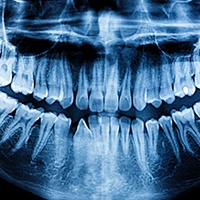

After your cleaning, Dr. Preet Taneja will give your mouth a thorough exam. The main goal of this exam is to detect any dental issues that may have occurred since your last appointment. She will check your mouth, head, neck, and jaw to make sure everything is functioning well, and she will also use digital X-Rays to get an in-depth look at your teeth. X-Rays are typically where she will be able to identify tooth decay and cavities. She also prevents and detects issues like:

Are Dental X-Rays Safe?

Some patients are wary of X-rays because they bring to mind radiation levels. However, thanks to our modern technology, there’s nothing to fear. We take all our X-rays digitally, which reduces radiation exposure by 90% while giving us clearer, faster images of your teeth and jawbone. We’ll always give you a lead apron to drape over the rest of your body as well to completely minimize your risk.